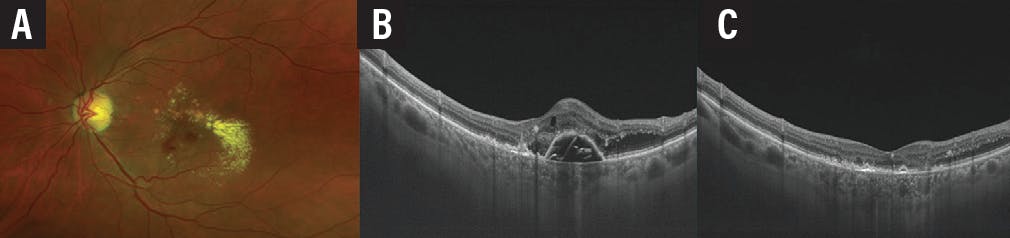

After 2 years of observation the patient complained of new onset of vision decline in the left eye. She presented with hard circinated exudates and retinal hemorrhage. OCT revealed reactivation of the RAP lesion. There was intraretinal and subretinal serous fluid, in addition to a significant PED. Three monthly aflibercept injections were performed, and the patient showed significant anatomic response soon after the first injection with improvement of VA to 20/25 OS (Figure 10).

<p>Figure 10. Fundus imaging (A) and OCT 2 years after presentation (B) show exudation in the left eye. OCT imaging after three intravitreal injections of aflibercept shows marked improvements (C).</p>

Figure 10. Fundus imaging (A) and OCT 2 years after presentation (B) show exudation in the left eye. OCT imaging after three intravitreal injections of aflibercept shows marked improvements (C).